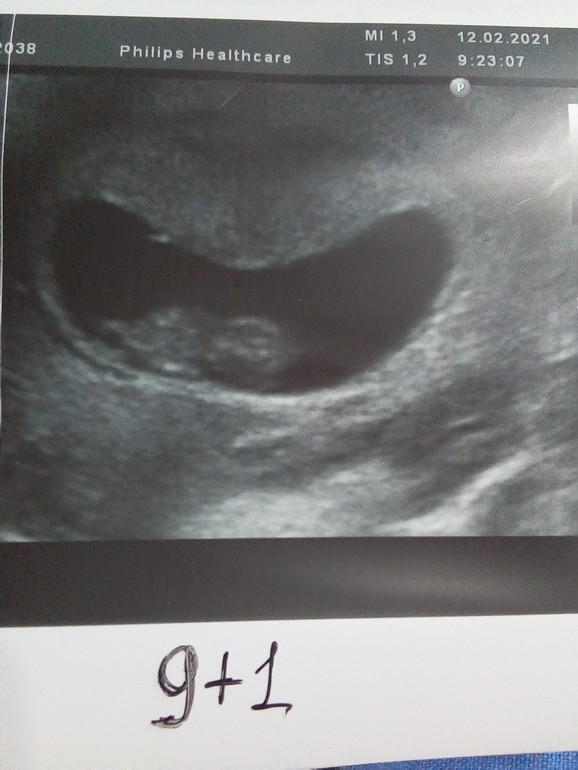

УЗИ 9+1

Всё хорошо. По УЗИ поставили срок 9+4:

ПЯ 38 мм, КТР 26 мм, ЧСС 186 уд/ мин, ЖМ 5 мм, преимущественная локализация плаценты по передней стенке в дне матки. Как думаете , кто по методу Рамзи? (фото сделано по животу) Пол поставила на удачу🤞